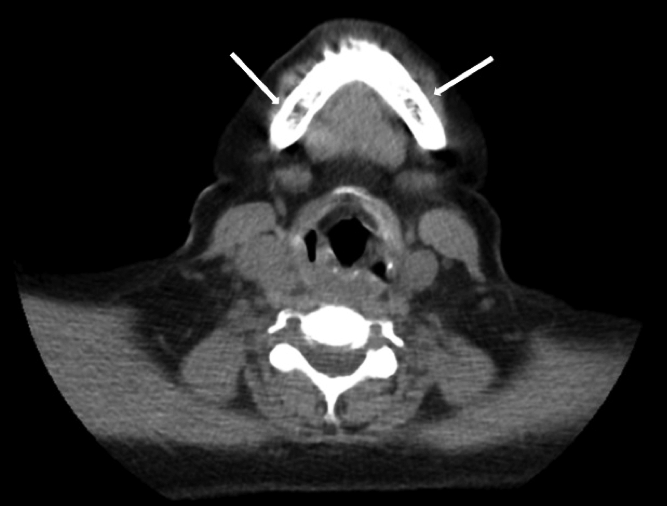

Ante la sospecha clínica de tumores pardos múltiples versus enfermedad metastásica se realiza IC con Oncología y en conjunto se solicitaron los siguientes estudios, que informaron como positivo: a) TAC de tórax, abdomen y pelvis (con contraste): leve enfisema centrolobulillar bilateral, opacidades nodulares con densidad de partes blandas (LSD y LSI). Resto de los órganos normales, no adenomegalias. Presencia de múltiples lesiones osteolíticas a nivel de todos los cuerpos vertebrales, esternón, región anterior de varias costillas, húmero, sacro, y porción visible de ambos ilíacos (Figuras 2, 3 . 4 A); b) TAC de cuello (con contraste): múltiples lesiones osteolíticas en la columna cervical.

Tiroides aumentada de tamaño a expensas del lóbulo derecho, múltiples formaciones nodulares, siendo la mayor con degeneración quística de 23x15mm. No adenomegalias (Figura 5); c) TAC de cerebro (con cte): Aumento difuso de la densidad ósea con múltiples lesiones osteolíticas en sacabocado (Figura 6); d) Proteinograma por EF: leve aumento en zona de alfa-2 globulina. e) Marcador tumoral (mama) CA 15,3:7,6 U/ml + examen ginecológico, ambos normales. f) Centellograma óseo total marcado con Tc 99: múltiples lesiones osteolíticas (Figura 7); g) Centellograma de paratiroides marcado con Sestamibi: captación selectiva en ambos polos inferiores sugestiva de tejido paratiroideo hiperplasiado. (Figura 8)